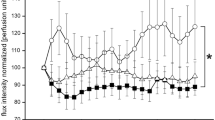

Spectroscopy and neurophysiological assessments

A significant positive association between both sural amplitude (ρ =0.61, p = 0.004) and nerve conduction velocity (ρ = 0.58, p = 0.006) and long TE NAA:creatine ratio signal was observed among participants with diabetes. In addition, the NAA:creatine ratio signal was significantly associated with peroneal latency (ρ = −0.53, p = 0.01), amplitude (ρ = 0.67, p = 0.001) and velocity (ρ = 0.37, p = 0.06) in this group. Similar correlations among participants with diabetes were noted with tibial nerve latency (ρ = −0.51, p = 0.02), but not with velocity (ρ = 0.23, p = 0.18). In this group, vibration detection threshold was related to NAA:choline ratio at a significant level (ρ = −0.70, p = 0.004), and we also observed a significant correlation between heart rate variability with deep breathing and NAA:creatine ratio (ρ = −0.46, p < 0.05). In addition, the NAA:creatine ratio was also found to relate to overall NCS (ρ = −0.53, p = 0.03) among diabetic participants.